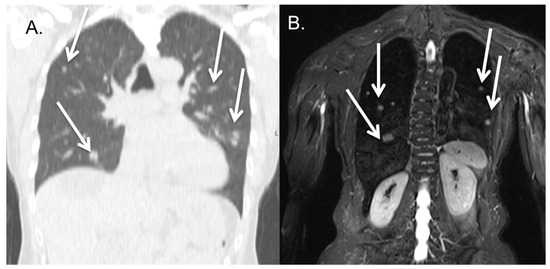

3.4. Lung Metastases